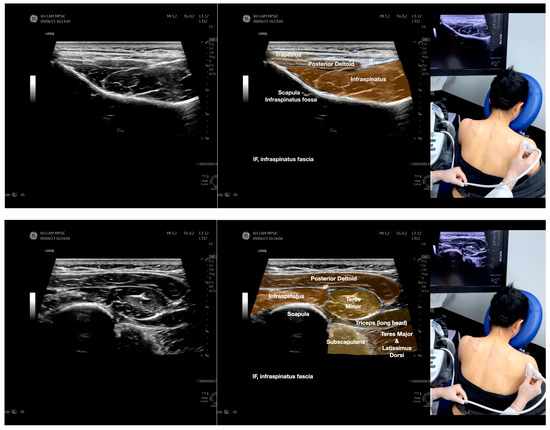

Figure 3.

Sonoanatomy of the lateral boarder of the scapular, its related muscles, and the infraspinatus fascia. Video S7 has demonstrated the step-by-step scanning techniques of these structures shown in this figure. Available online: https://www.dropbox.com/s/891m19vvw6bak34/Figure%203.docx?dl=0 (accessed on 1 January 2023).